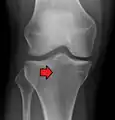

Subtle tibial plateau fracture on an AP X ray of the knee

Lipohemarthrosis due to a tibial plateau fracture- A tibial plateau fracture seen on X-ray